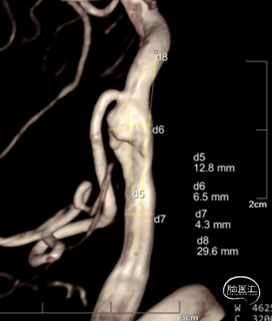

3D造影:动脉瘤处有明显的凹陷,符合夹层内膜瓣表现;PICA从动脉瘤远端发出,动脉瘤大小约6.5×12.8mm,受累椎动脉直径约4.3mm,覆盖远近端达正常血管约需30mm支架长度。